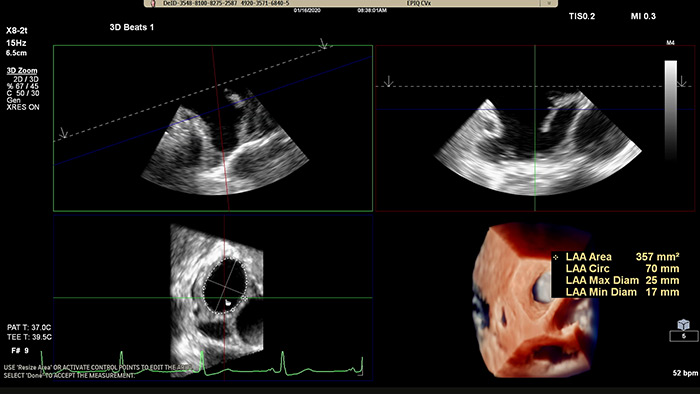

Rapidly acquire LAA orifice measurements in both traditional rendering or in TrueVue Glass rendering, with 3D Auto LAA